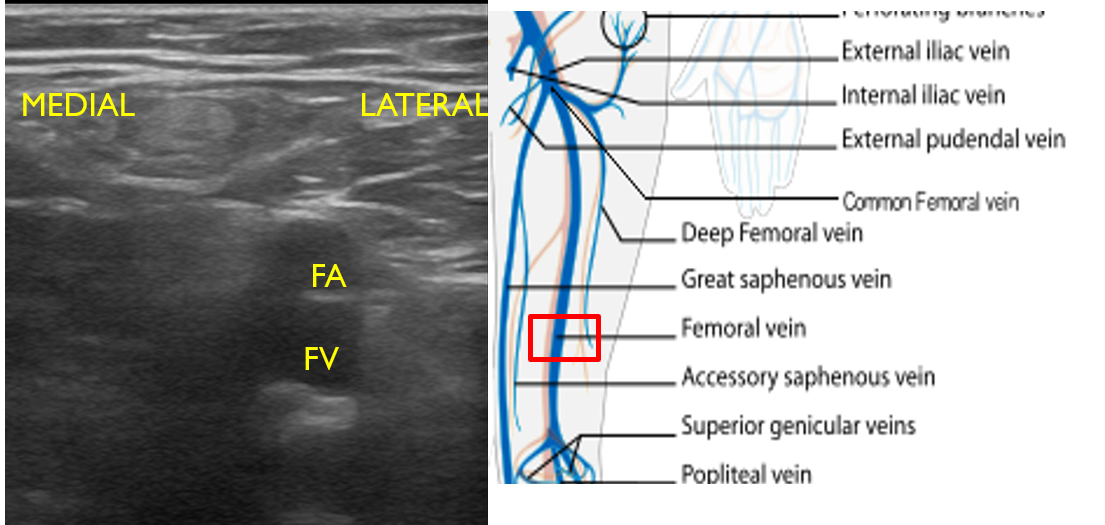

- Slide the transducer another 1 to 2 cm (3-4 cm distal to the inguinal ligament) to the junction of the DFV and FV. You will also see the CFA branch into the FA and DFA (Fig. 12). This constitutes completion of evaluation of “region 1.”

- Figure 12. Visualization of the DFV and FV just distal from where they converge into CF with transducer orientation indicated (red rectangle).

- For continual evaluation along the proximal leg, slide the transducer along the medial thigh, keeping the FA and FV in view. The FA will be superficial to the FV (Fig. 13). Compress at short intervals along the course of the vein until the pair dives deep through the adductor canal, just proximal to the knee.

- Figure 13. Femoral artery and vein seen in mid to distal upper leg with transducer orientation indicated (red rectangle).